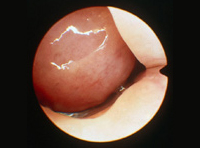

La cirurgia endoscòpica nasosinusal és una intervenció que agrupa variades tècniques quirúrgiques. Totes elles tenen en comú les actuacions quirúrgiques en l'interior del nas, visualitzant i manipulant les estructures a través de les foses nasals, utilitzant instruments òptics (endoscopis i fonts d'il·luminació amb possibilitat de connectar-se a sistemes de televisió i enregistrament en vídeo) i instrumental quirúrgic adequat.

La cirurgia té per objectiu la reparació de les estructures anatòmiques anòmales i/o l'extirpació de les lesions que alteren les funcions normals del nas, dels sinus paranasals i dels demés òrgans veïns, i que són els responsables de causar molèsties al pacient. Els símptomes són variats i de diferent intensitat, essent els principals la dificultat per respirar pel nas, els dolors a la cara i el cap, la sensació de sequedat nasal o la presència persistent de mucositat nasal més o menys espessa, l'hemorràgia nasal, el llagrimeig persistent, les alteracions en la visió o en l'audició i les alteracions en l'olfacte.